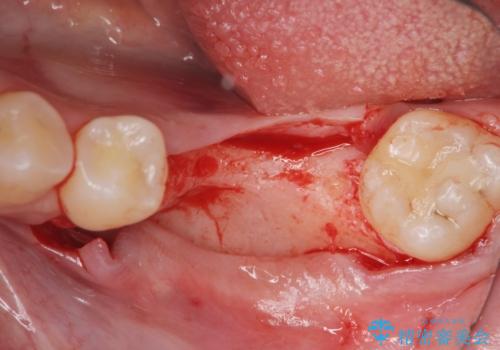

骨造成を行い安定したインプラントの環境を整える治療を計画します。

インプラントの長期的な予後を見込むには、インプラント周囲の安定した十分な骨量や清掃性、角化歯肉の存在が重要です。